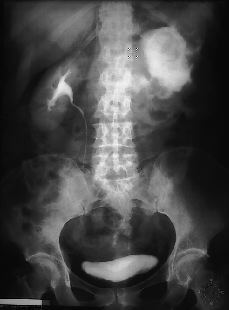

Radiología Osteosarcoma extraesquelético. A propósito de un caso

Osteosarcoma extraesquelético. A propósito de un caso

Extraskeletal osteosarcoma. A case report